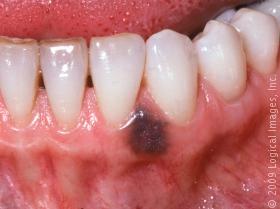

What is this?

Amalgam tattoo (ha! and you thought it was oral melanoacanthoma)